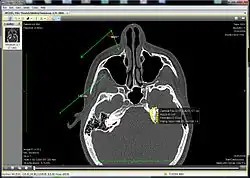

Ginkgo CADx displaying a CT | |